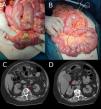

A 66-year-old woman who attended the Emergency Department due to colic-type abdominal pain in the epigastric region of four days’ evolution, with associated nausea and vomiting. She presented a fever of 38 °C, and in the physical examination the abdomen was soft and depressible, with diffuse pain to palpation. Blumberg’s sign was positive. The analysis revealed leukocytosis (15.9 × 109/l) and elevated C-reactive protein (CRP) (3.3 mg/dl). Abdominal and pelvic computed tomography (CT) was performed, finding pneumoperitoneum, intra-pelvic free fluid and increased mesenteric fat density in the left hemiabdomen. Diverticulosis was also found in the sigmoid colon. The patient’s initial diagnosis was perforated sigmoid diverticulitis, and the decision was made to perform emergency surgical treatment. Intraoperatively, disseminated peritonitis was observed in all quadrants with inter-loop collections and multiple jejunal diverticula (10 diverticula distributed in the jejunum, beginning immediately distal to the duodenojejunal flexure) with a large perforation of one diverticulum on the mesenteric face of the jejunum at 80 cm from the duodenojejunal flexure (Fig. 1). The jejunal fragment with the perforated diverticulum was resected and termino-terminal (T-T) mechanical anastomosis carried out. The postoperative period was without incident and the patient was discharged on day seven after the procedure. On reviewing the CT following the surgery, it was possible to identify the diverticula (Fig. 1B). Subsequently, the anatomopathological study confirmed jejunal diverticular disease with perforation, as well as marked inflammation of the intestinal mesentery.

1A) Intraoperative image: perforation of a single large distal jejunal diverticulum. 1B) Intraoperative image: multiple large jejunal diverticula, on the mesenteric face, from practically the duodenojejunal flexure to 80 cm from the same (black circle). 1C and 1D) Abdominal and pelvic CT image, axial view. The image shows the jejunal diverticula (red arrows).